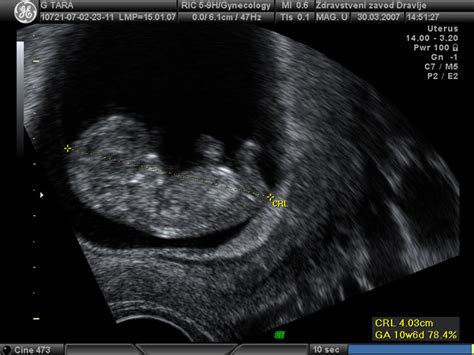

Ginekolog opravi vaginalni ultrazvok, s katerim potrdi nosečnost. Določi, če je nosečnost v maternici ali gre za morebitno izvenmaternično nosečnost. Določi število plodov in vitalnost (navzočnost plodovih srčnih utripov), dolžino ploda in s tem pričakovani termin poroda. Pregleda tudi samo maternico in oba jajčnika.